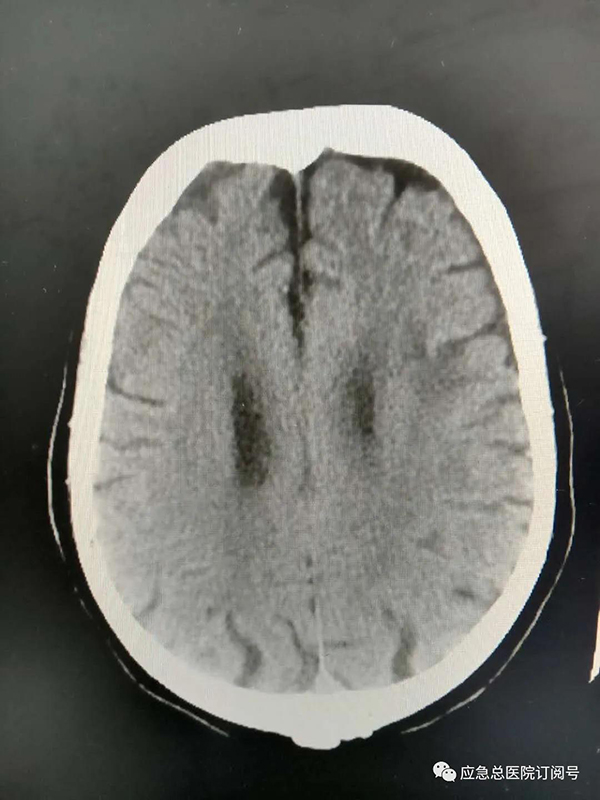

患者赵某,女性,82岁,因言语不清伴右侧肢体无力1.5小时后来我院急诊。经我院急诊、脑卒中双绿色通道的相关检查后,神经内科主任医师周卫东以及主治医师刘长春,在确保防护措施到位的前提下,对患者进行了会诊,给出了急性脑梗死的诊断,并及时对其进行了静脉溶栓。溶栓前,患者混合型失语,右上下肢肌力0级;静脉溶栓后,病人言语流利,右上下肢肌力5级,恢复良好。出院两周后,回医院随诊,患者非常满意。